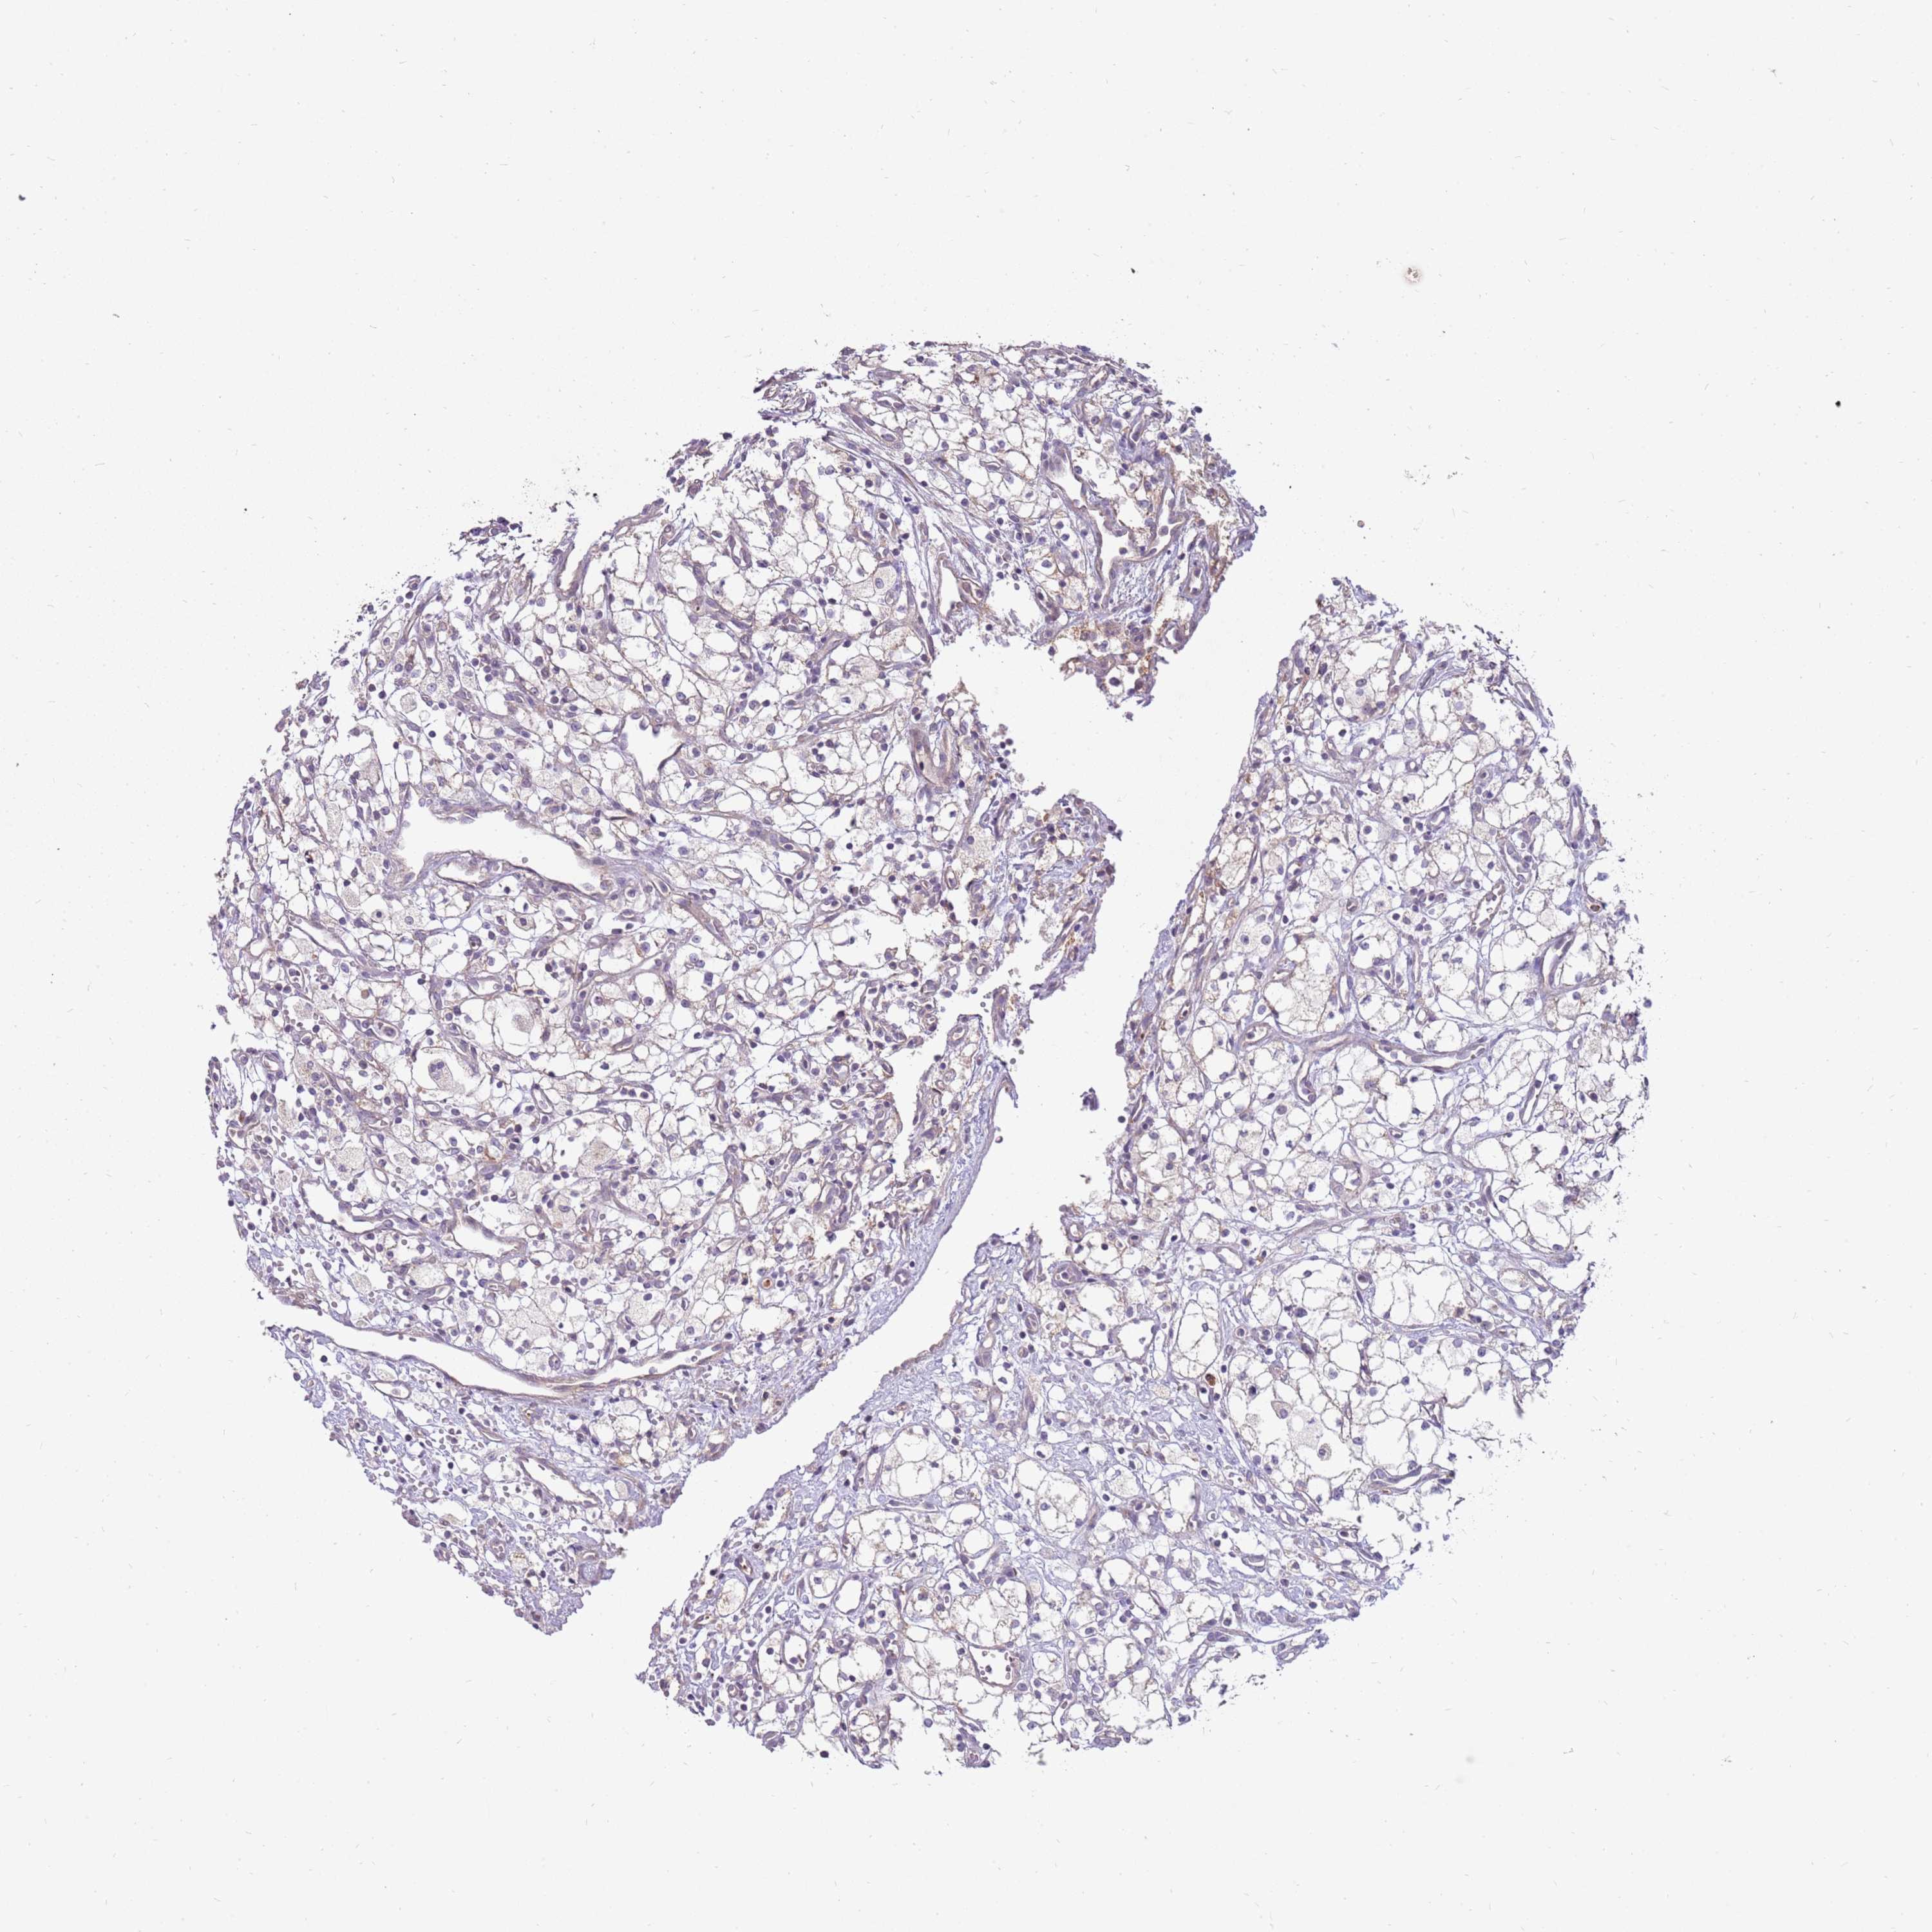

KIDNEY RENAL PAPILLARY CELL CARCINOMA (TCGA) - Interactive survival scatter ploti

The Survival Scatter plot shows the clinical status (i.e. dead or alive) for all individuals in the patient cohort, based on the same data that underlies the corresponding Kaplan-Meier plots. Patients that are alive at last time for follow-up are shown in blue and patients who have died during the study are shown in red.

The x-axis shows the expression levels (FPKM) of the investigated gene in the tumor tissue at the time of diagnosis. The y-axis shows the follow-up time after diagnosis (years). Both axes are complimented with kernel density curves demonstrating the data density over the axes. The top density plot shows the expression levels (FPKM) distribution among dead (red) and alive patients (blue). The right density plot shows the data density of the survived years of dead patients with high and low expression levels respectively, stratified using the cutoff indicated by the vertical dashed line through the Survival Scatter plot. This cutoff is automatically defined based on the FPKM cutoff that minimizes the p-score. The cutoff can be changed by dragging the vertical line or by entering a cutoff value in the square labeled "Current cut-off".

Under the Survival Scatter plot the p-score landscape (black curve; left axis) is shown together with dead median separation (red curve; right axis). Dead median separation is the difference in median mRNA expression between patients who have died with high and low expression, respectively. It is calculated as follows: median FPKM expression of dead patients with high expression - median FPKM expression of dead patients with low expression. This is intended to aid the user in visually exploring custom cutoffs and the associated p-scores and dead median separation.

Individual patient data is displayed and can be filtered by clicking on one or more of the category buttons on the top of the page. Categories describing expression level and patient information include: high, low, alive, dead, female, male and tumor stages. The scale of the x-axis can be toggled between linear and log-scale by clicking on the "x log" button. Mouse-over function shows TCGA ID, patient information and mRNA expression (FPKM) for each patient.

& Survival analysisi

Kaplan-Meier plots summarize results from analysis of correlation between mRNA expression level and patient survival. Patients were divided based on level of expression into one of the two groups "low" (under cut off) or "high" (over cut off). X-axis shows time for survival (years) and y-axis shows the probability of survival, where 1.0 corresponds to 100 percent.

LRFN3 is not prognostic in Kidney Renal Papillary Cell Carcinoma (TCGA)

Best expression cut offi

Based on the FPKM value of each gene, patients were classified into two groups and association between prognosis (survival) and gene expression (FPKM) was examined. The best expression cut-off refers the FPKM value that yields maximal difference with regard to survival between the two groups at the lowest log-rank P-value. Best expression cut-off was selected based on survival analysis .

When clicking on this number, the vertical dashed line indicating cut-off, the interactive survival plot, and the Kaplan-Meier curve will be adjusted to show results based on the best expression cut-off.

: 3.27